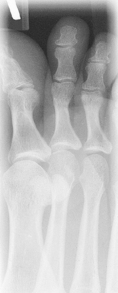

• Supine or seated with plantar surface of foot flat on IR, aligned lengthwise to portion of IR being exposed

• Supine or seated with foot centered lengthwise to portion of IR being exposed

• Oblique foot 30°–40° medially, support with 45° radiolucent angle block and sandbags to prevent slippage

• Note 1: A higher arch requires nearer 45° oblique and a low arch “flat foot” nearer 30°.

• Note 2: A 30° lateral oblique projection will demonstrate the space between 1st and 2nd metatarsals and between 1st and 2nd cuneiforms.